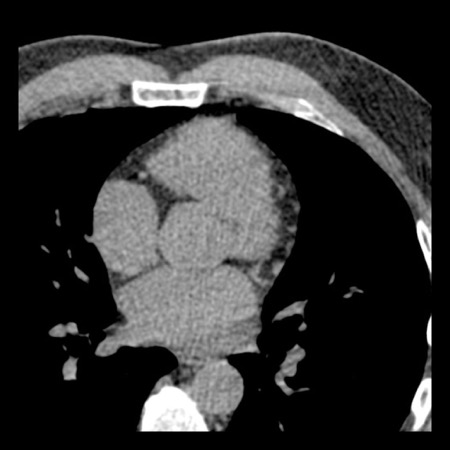

case 3 – Calcium score 0 and severe stenoses.

First, scroll through the CTA images.

How would you describe the findings on the coronary CTA?

The findings are:

- The total calcium

score of 0 indicates the absence of calcified plaque in the coronary

tree. - Severe stenosis

(70-99%) in the mid LAD and D2 branch.